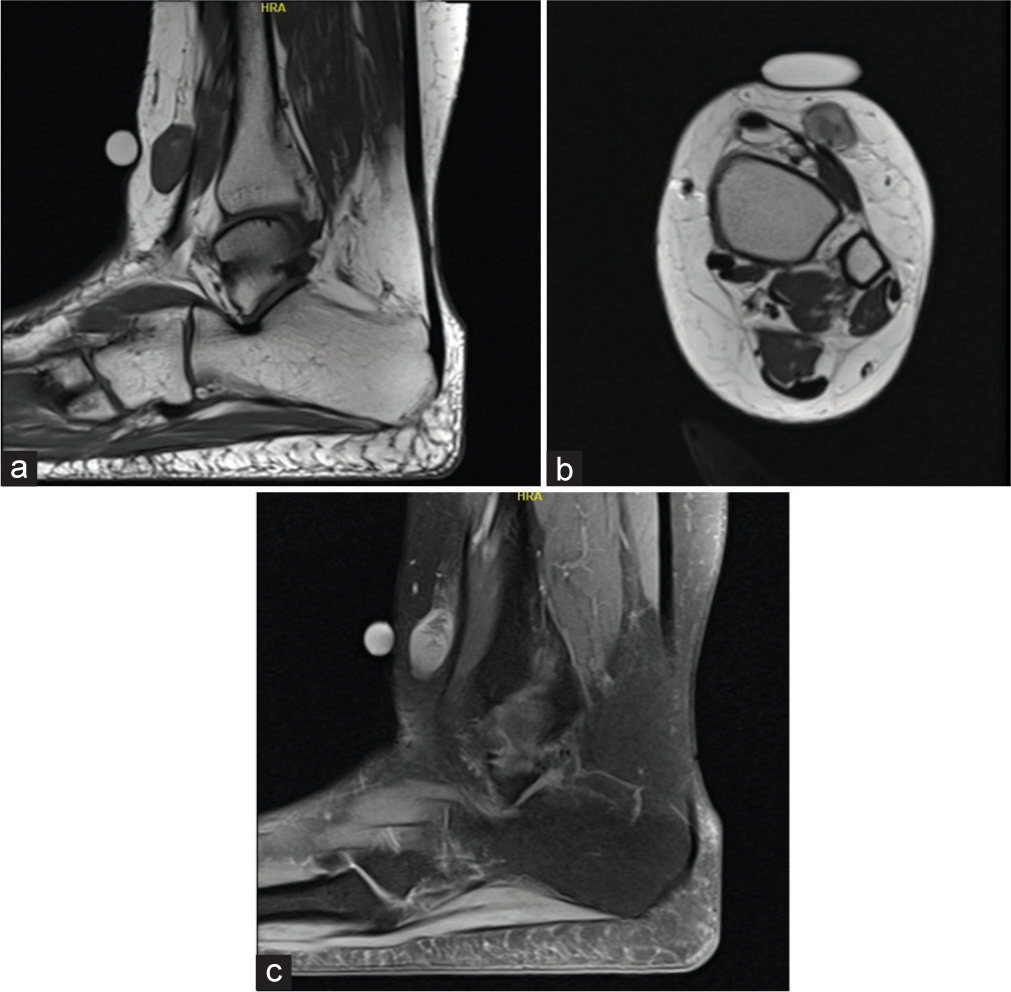

3.1 RM

- Masa de partes blandas agresiva o sospechosa, sin rasgos verdaderamente específicos.

- Heterogeneidad y posible necrosis según grado y tamaño.

- La imagen orienta extensión y resecabilidad, pero rara vez cierra el subtipo.

3.2 Mensaje práctico

En esta variante, la imagen no distingue bien entre EMPNST, melanoma, sarcoma epitelioide u otros sarcomas. La confirmación depende de la patología.